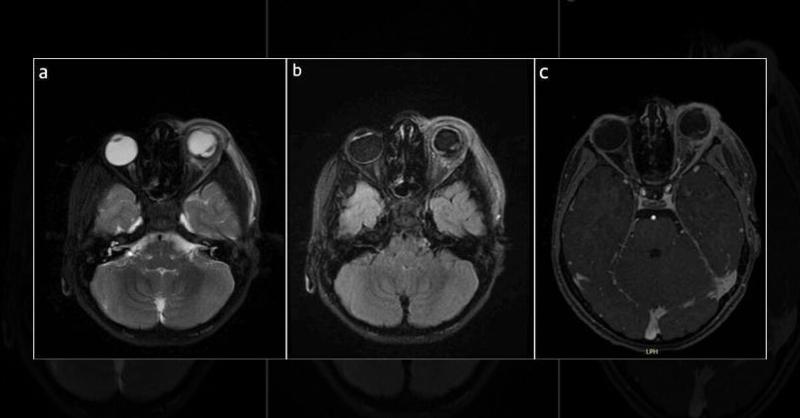

A nine-year-old boy came to the eye clinic with left eye pain and swelling after a sheep needle injury. Initially reassured, he returned on day 3 with worsening symptoms. Further examination at another facility revealed a serious issue: vitreous hemorrhage and retinal detachment with a large tear. He received antibiotics and was referred to our cen